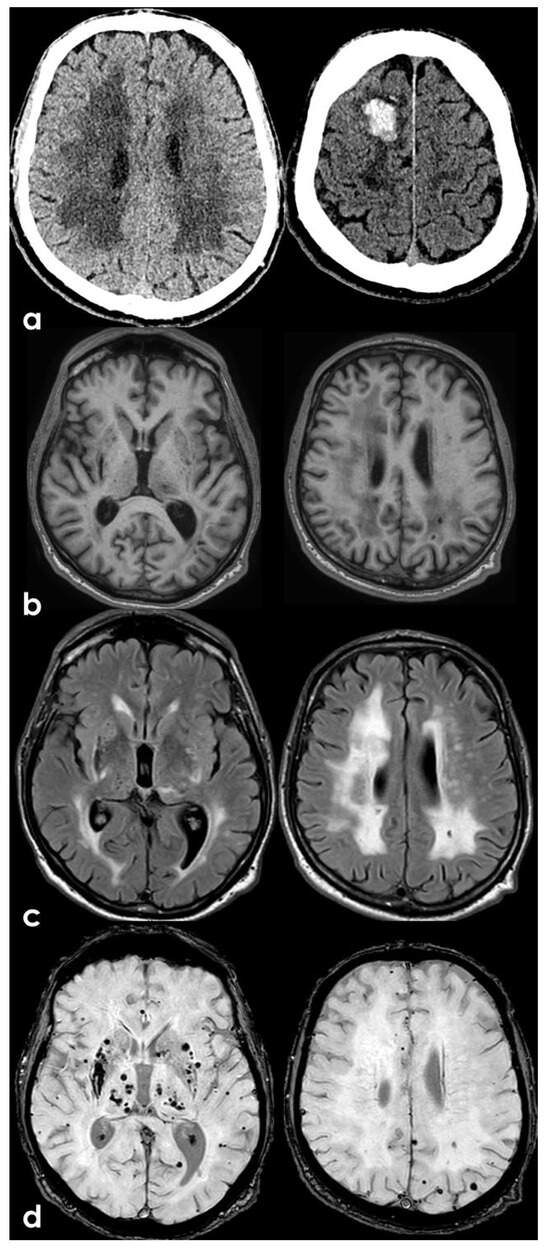

Background: The relationship between inflammatory markers and cerebral small vessel disease (CSVD) in patients with acute ischaemic stroke (AIS) remains unclear. This study aimed to investigate the association between simplified inflammatory biomarkers and neuroimaging markers of CSVD. Methods: This retrospective cohort study included patients with AIS who had symptom onset within 72 h and underwent MRI brain between January 2019 and December 2023. The associations between tertiles (T) of the neutrophil-to-lymphocyte ratio (NLR) and CSVD markers were studied using multinomial logistic regression. Functional outcomes at discharge and 90 days, as measured by the modified Rankin Scale (mRS), were also evaluated. Results: A total of 299 eligible patients were included, with a mean age of 65.7 ± 13.8 years and 55.5% (166/299) were male, and categorised into three tertiles of NLR (T1: 101, T2: 101, T3: 97). Patients with a higher NLR tertile had more admission NIHSS (T3 vs. T1: 3 (2, 5) vs. 2 (1, 3), p = 0.005). NLR was associated with an increased risk of ≥5 lobar cerebral microbleeds (CMBs) in an unadjusted model (T3 vs. T1: relative risk ratio (RRR), 5.69 (95% confidence interval (CI) 1.21–26.68); p = 0.03); however, this was not significant when adjusted for potential confounders (RRR 3.86; 95% CI 0.79–18.89; p = 0.10). No significant associations were observed in the remaining neuroimaging markers of CSVD. Patients in the T2 of NLR had a higher likelihood of achieving an mRS of 0–1 at 90 days (RRR 2.16; 95% CI 1.05–4.44; p = 0.04) compared to those in T1. Conclusions: In AIS, admission NLR showed a possible association with higher lobar CMB burden in unadjusted analyses, but this was not robust after adjustment, and no consistent relationships were observed with other CSVD markers. Associations with functional outcomes were not uniform across tertiles, and the apparent benefit in the middle NLR tertile should be interpreted cautiously as a potentially non-linear or chance finding, indicating that NLR is not a reliable independent imaging or prognostic marker in this cohort. Full article